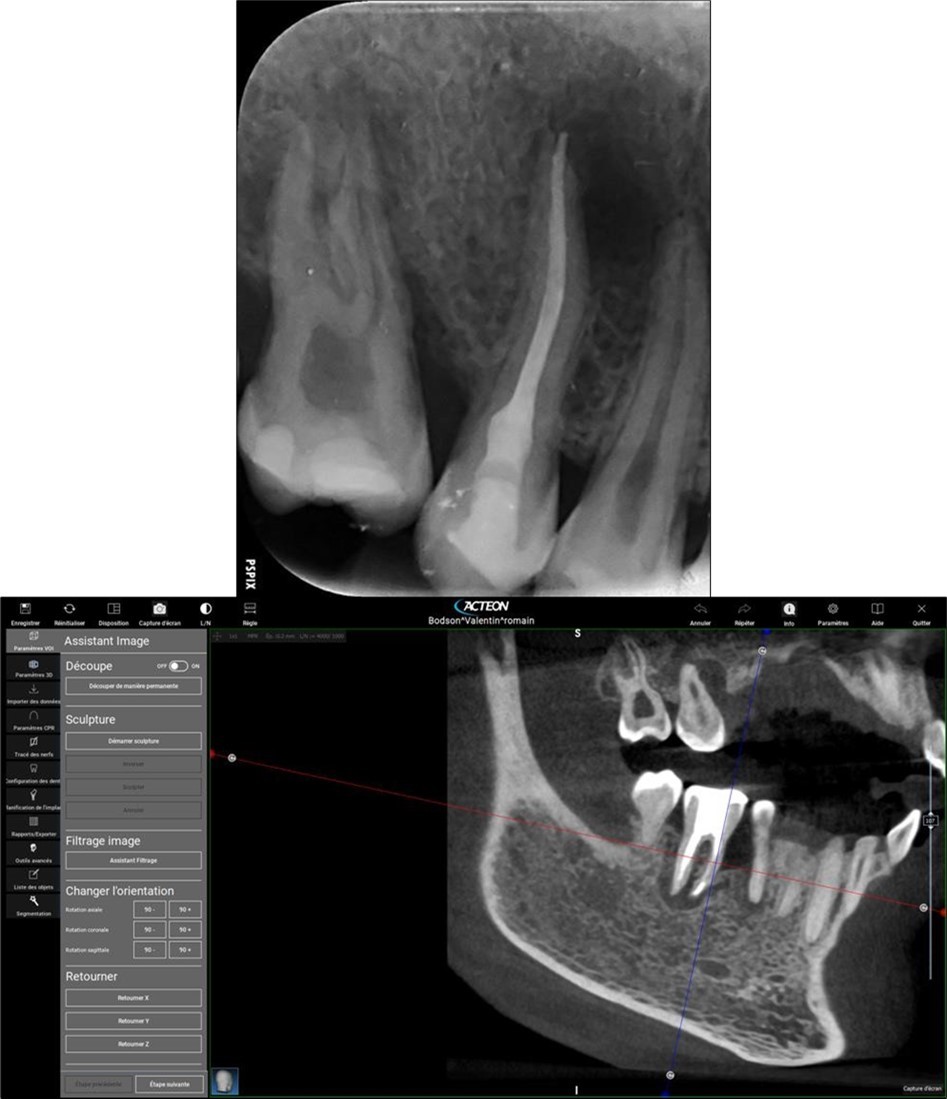

Periapical radiography (phosphorus number 2 plaque and X-MIND® Unity; Acteon) and cone-beam computed tomography (X-MIND® 3D; Acteon) (80 × 80, 150 Micron) were performed and showed periapical lesions on teeth 14, 15, 16, 24, 25, 26, 35, 36, and 46, as well as advanced endo-perio lesions on teeth 26 and 16. orthopantomogram (X-MIND® 3D; Acteon) and bitewings (phosphorus number 2 plaque and X-MIND® Unity; Acteon) also showed wide pulp chambers and roots canals. Figure 1, Figure 2

Figure 1.1 and 2 show a wide pulp chamber, root canals, and several restorations.

Figure 2.2. 3, 4, and 5 show periapical lesions on teeth 15, 16, 24, 25, 26, 35, 36, and 46.

Complete healing of periapical lesions and treatment of teeth 26 and 16 with advanced endo-perio lesions posed challenges due to the patient’s delayed supplementation. In this case, surgical endodontic procedures and the extraction of teeth with advanced endo-perio lesions were considered risky because of the underlying metabolic healing impairment. Figure 3

Figure 3.6. 7, 8, 9, and 10 showing postoperative periapical radiographs of these endodontic treatments.